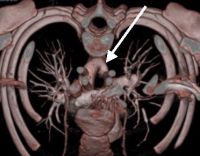

Мультиспиральная компьютерная ангиография аорты и магистральных сосудов рекомендуется для получения трехмерного изображения, на котором отчетливо видна двойная сосудистая дуга. Используя МСКТ, диаметр аорты измеряется на разных уровнях, и определяются области атрезии.

КТ сердца. Двойная дуга аорты. Стрелки указывают на правую и левую дуги аорты примерно одинакового размера.